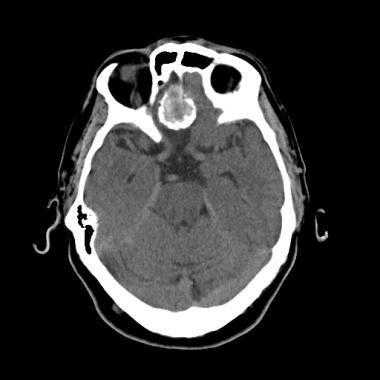

(Слева) Бесконтрастная КТ, аксиальный срез: определяется дольчатое гиперденсное объемное образование, расположенное по ходу намета мозжечка справа.

(Справа) МРТ, FLAIR, аксиальный срез: у этого же пациента визуализируется гипоинтенсивное многодольчатое объемное образование с перифокальным отеком и масс-эффектом на IV желудочек.